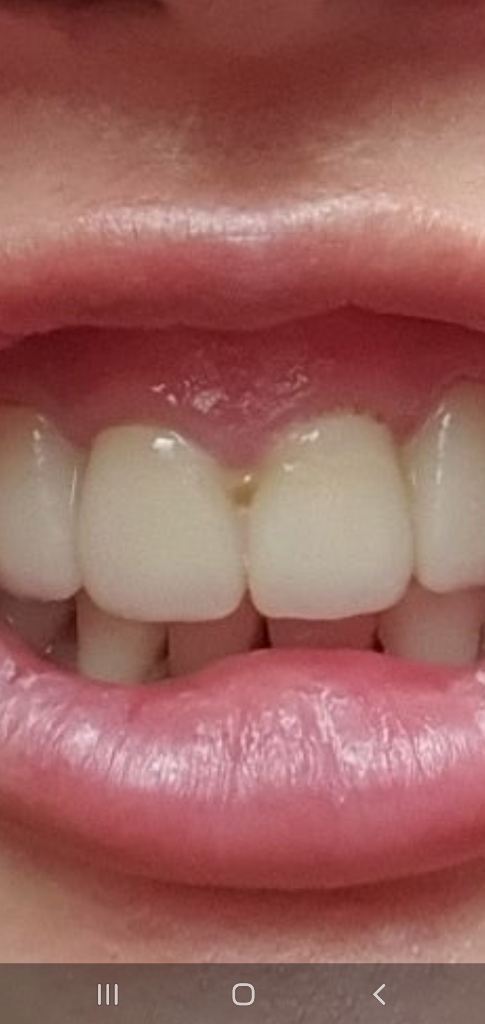

이렇게 아침에..저리 이사이 에 염증이 있습니다.

지금 현상태 잇몸은 이렇습니다.